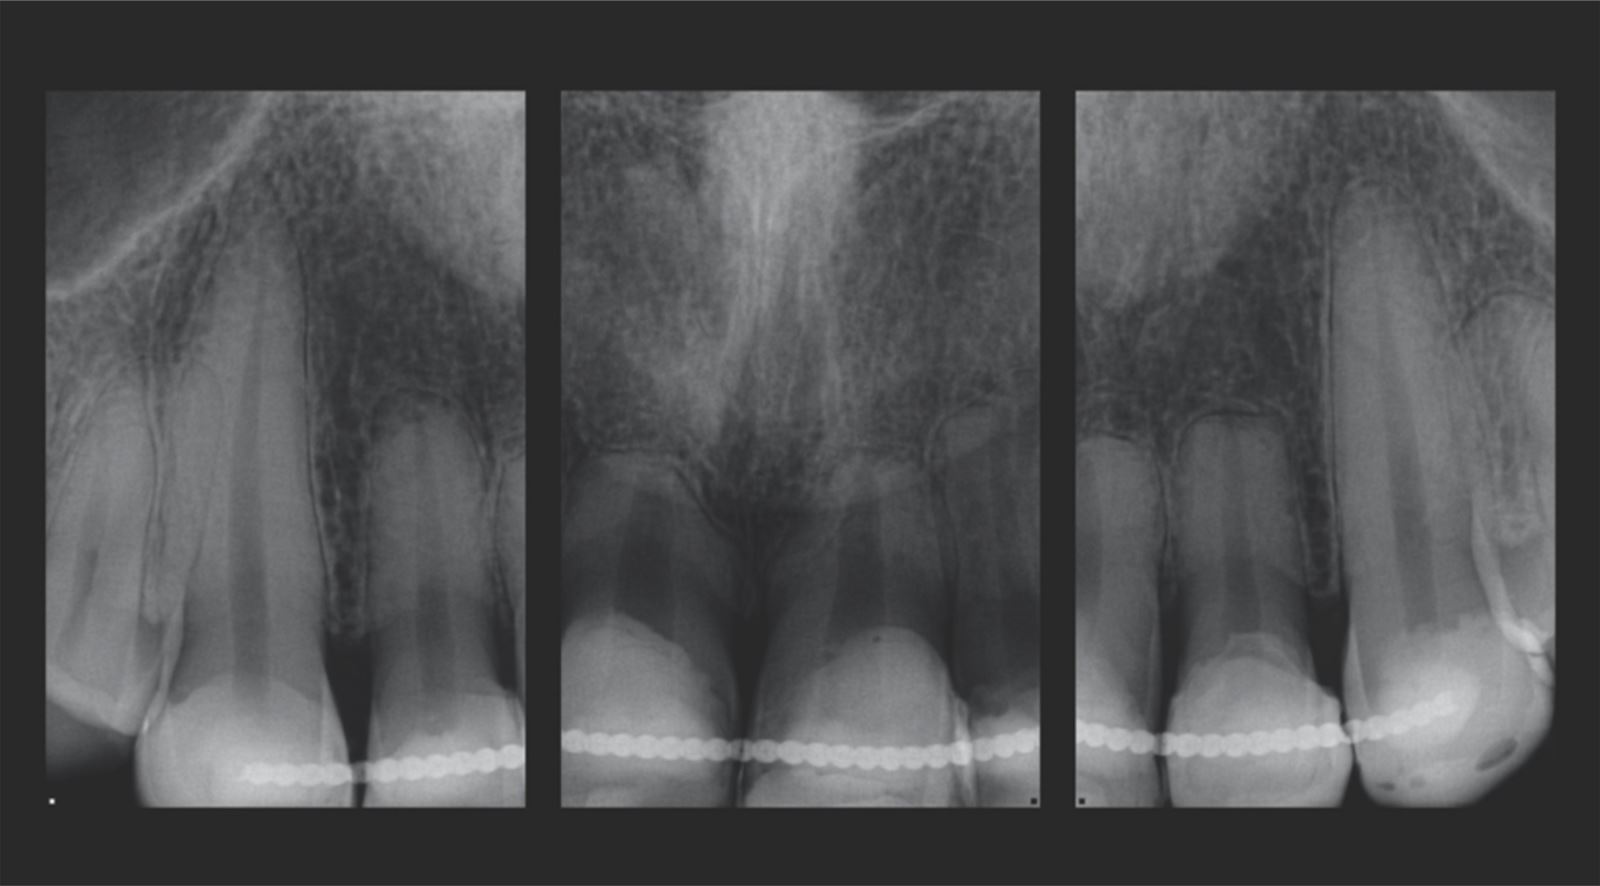

Mladá žena vo veku okolo 20 rokov, ktorú trápila diskolorácia horných frontálnych zubov po skoršej traume, vyhľadala ošetrenie u Dr. Jaleeny Fischer-Jessop, DDS, MBA. Hľadala riešenie, ktoré by obnovilo jej úsmev. Pacientka bola ošetrená konzervatívnou a cenovo dostupnou metódou: kompozitnými fazetami bez preparácie, priamym bondingom. Dr. Fischer-Jessop zvolila tento postup na prekrytie diskolorácie a zjednotenia horných zubov s dolnými frontálnymi – bez nutnosti invazívnejších výkonov, ako sú implantáty, alebo nákladných laboratórne zhotovovaných faziet. Na zosvetlenie zubov boli vybrané odtiene B1D a Enamel White (EW) a odtieň Universal Body (UB) kompozitu Transcend™ bol použitý na prirodzené splynutie okraja v cervikálnych oblastiach.

Pacientka v 20 rokoch s anamnézou traumy horných frontálnych zubov. Napriek tomu, že trauma prebehla, zuby zostali stabilné, takže implantáty neboli nutné.